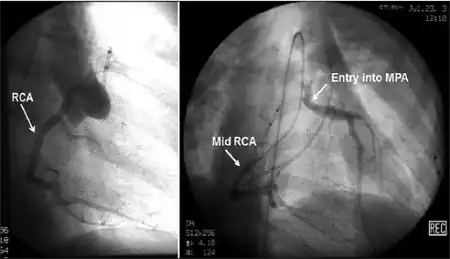

| Possible communication between left coronary artery and pulmonary artery in a 45-year-old woman with Bland-White-Garland syndrome. | |

Anomalous left coronary artery from the pulmonary artery (ALCAPA, Bland-White-Garland syndrome or White-Garland syndrome) is a rare congenital anomaly occurring in approximately 1 in 300,000 liveborn children. The diagnosis comprises between 0.24 and 0.46% of all cases of congenital heart disease.[1] The anomalous left coronary artery (LCA) usually arises from the pulmonary artery instead of the aortic sinus. In fetal life, the high pressure in the pulmonic artery and the fetal shunts enable oxygen-rich blood to flow in the LCA. By the time of birth, the pressure will decrease in the pulmonic artery and the child will have a postnatal circulation. The myocardium which is supplied by the LCA, will therefore be dependent on collateral blood flow from the other coronary arteries, mainly the RCA. Because the pressure in RCA exceeds the pressure in LCA a collateral circulation will increase. This situation ultimately can lead to blood flowing from the RCA into the LCA retrograde and into the pulmonary artery, thus forming a left-to-right shunt.[2]

Historically ALCAPA was diagnosed with conventional angiography. Today echocardiography is easily used. It can provide direct visualisation of the anomalous coronary artery and other associated structural abnormalities, and it can also assess myocardial function .The use of pulse and color-flow doppler can sometimes visualise reversal flow in the pulmonic artery. Other non-invasive methods used are computed tomography (CT) as well as magnetic resonance imaging (MRI) which enable a direct visualisation of the arteries as well as the myocardial viability.[3]